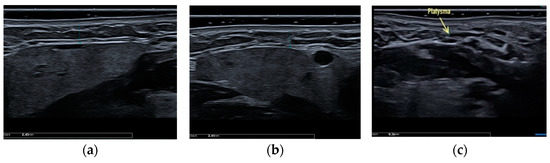

Clinical case #1. During the study, a 43-year-old female patient was examined with a 9 MHz linear transducer of soft tissues of the lower third of the face and neck without pressure, in an upright position; the skin, subcutaneous tissue, and m. platysma were visualized and the degree of their participation in the formation of deformity was estimated. Excessive accumulation of adipose tissue was determined along the contour of the lower jaw from both sides (Figure 1a,c) as well as in the submental area above and below the platysma muscle (Figure 1b).

Figure 1.

B-mode ultrasound examination of the soft tissues of the lower third of the face and neck. A 9 MHz linear transducer. Excessive accumulation of adipose tissue in the submental area, above and below the platysma muscle (b), and along the contour of the lower jaw from both sides (a,c).

Accordingly, it is sufficient to remove this excess adipose tissue by liposuction or lipectomy to correct the contours of the lower third of the face and neck.